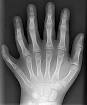

OMIM Entry - MECKEL SYNDROME, TYPE MKSA number sign is used with this entry because Meckel syndrome type is caused by homozygous or compound heterozygous mutation in a gene encoding a. The most common features are enlarged kidneys with. Meckel-Gruber-Syndrom Beim Meckel-Gruber-Syndrom (MKS) handelt es sich um eine autosomal- rezessive vererbte Erkrankung. Orphanet: Meckel syndrome Meckel Gruber syndrome Zusammenfassung. Meckel-Gruber-Syndrom - DocCheck Flexikon Das Meckel-Gruber-Syndrom beschreibt ein Syndrom aus schweren, angeborenen Fehlbildungen, die mit dem Leben nicht vereinbar sind und zum raschen. Meckel-Gruber-Syndrom Medizin-Lexikon - Das Meckel-Gruber-Syndrom ist eine vererbte Erkrankung, die charakterisiert ist durch Nierenzysten, Entwicklungsstörungen und Störungen des.

Orphanet: Meckel syndrome Meckel Gruber syndrome

OMIM Entry - MECKEL SYNDROME, TYPE MKS1

Meckel-Gruber-Syndrom